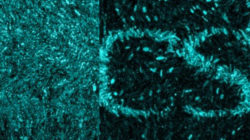

Ja sigui alcohol, tabac, cocaïna o cànnabis, les drogues creen una dependència de la que és difícil sortir-ne. Expliquem com funcionen les addiccions al cos i quina recerca s’està portant a terme al respecte.